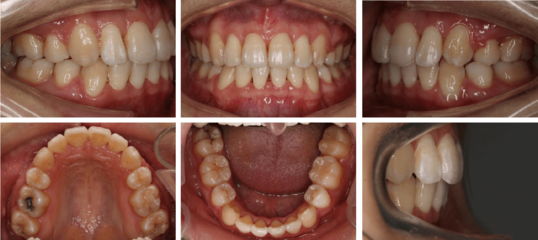

正畸的流程:【点击咨询在线口腔助手专业解答】1。初诊:患者想要改善牙齿畸形后,首先要进行初诊,好好沟通,让对方有一个非常详细的了解。2.资料收集:通过沟通后拍X线片,可以定位侧位头影、全景片、制作牙颌模型、拍摄颌面及口内牙齿照片。3.制定计划和方案:通过医生对求美者综合情况的了解,综合分析,制定最适合求美者的矫正方案,可以使效果更好。

1初诊正畸医生初步检查是否需要进行正畸治疗,并指出存在的问题和最终可以达到的效果。然后你需要和你的医生沟通,确定是否进行正畸治疗。2收集资料临床资料由正畸医生收集,拍摄口腔全景X线片,以及面部、牙齿、口腔各个角度的照片。医生还需要给你的牙齿做个模型,在牙齿上涂上速凝胶,咬1-2分钟后取出。3确定方案与正畸医生详细讨论存在的问题和治疗方案,是否需要拔牙,拔哪些牙,用什么材料,最终疗效如何,疗程多久,费用是否合适,最终达成双方满意的治疗方案并签字备案。

正畸过程可以分为这几个阶段:1。咨询:包括治疗前的临床检查、诊断资料的收集(如石膏模型、面部外观及口腔牙列摄影、面部及牙列X线检查等。),对病历的诊断分析,治疗方案的制定,对患者的讲解和讨论。2.开始正畸治疗:治疗方案确定后,医生会根据患者的病情和要求选择合适的托槽,并进行相应的调试、粘接和施力。正畸治疗首先从牙齿的治疗开始,然后一般每个月就诊一次。具体时间由医生根据治疗需要决定,每次就诊时会做必要的检查和记录。